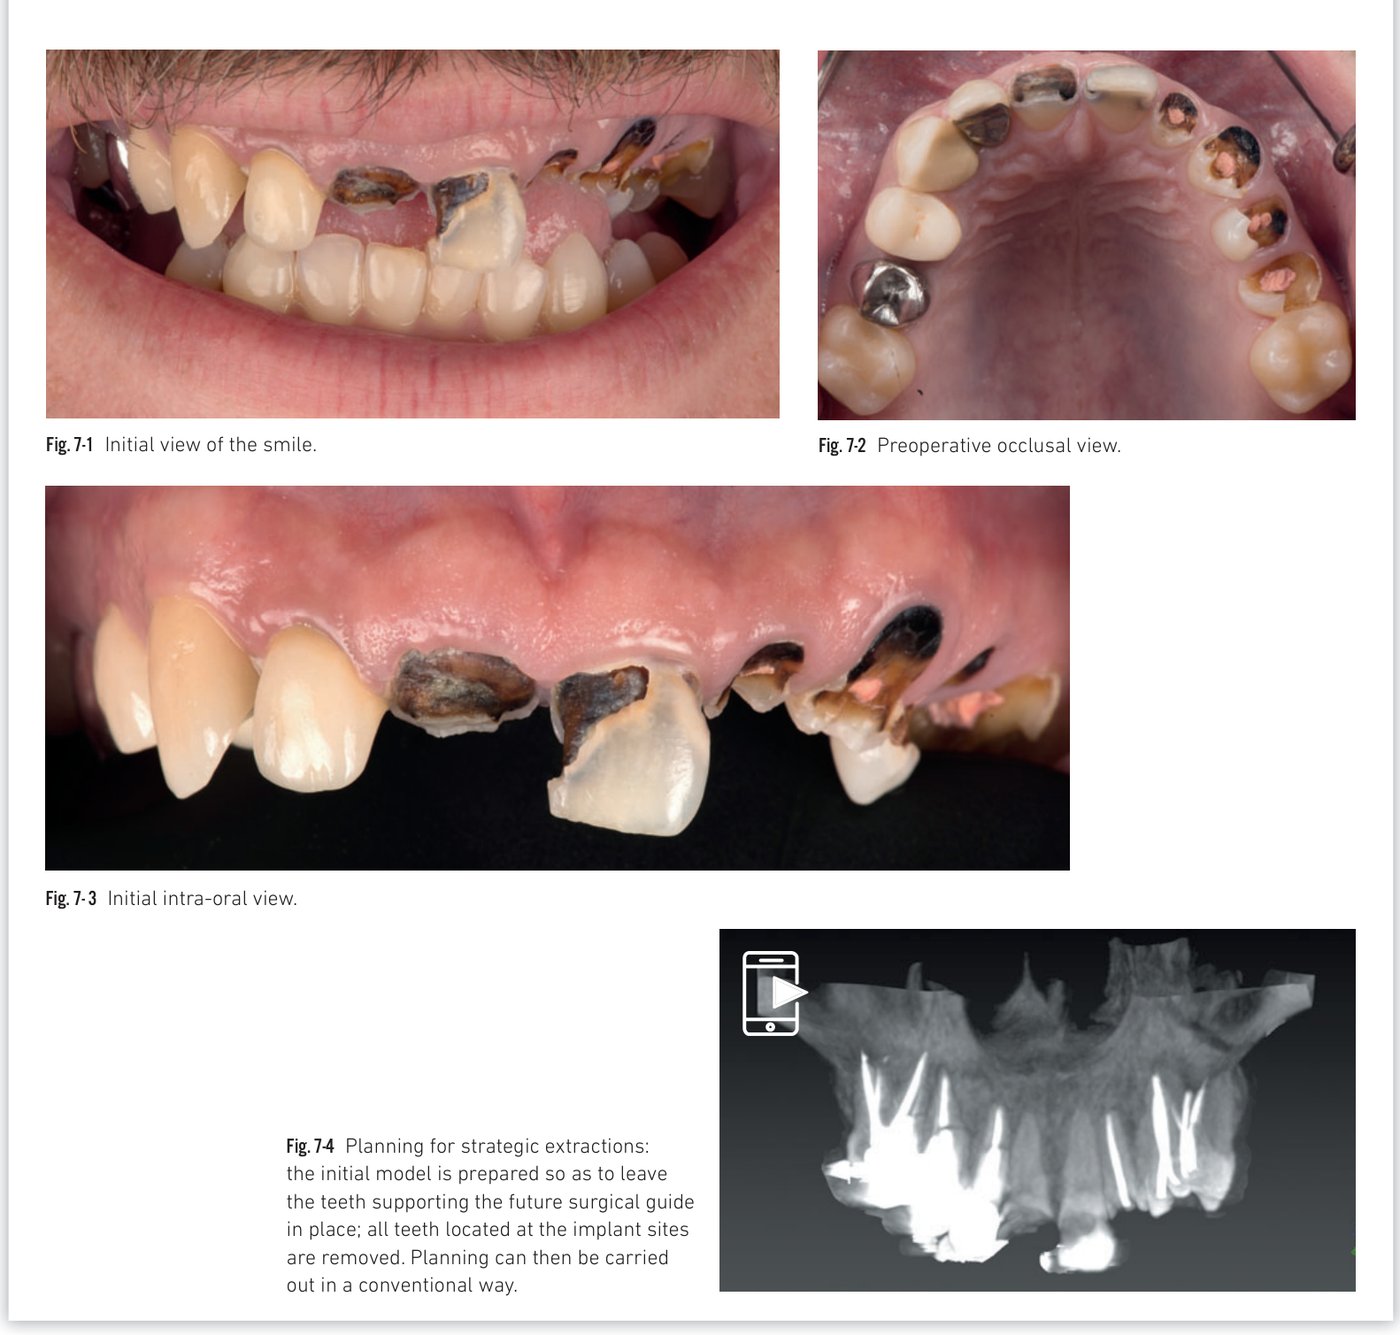

Clinical situation 7

The concept of strategic extractions

The transition to complete or widespread edentulism often makes surgical guide stabilization challenging. Tooth-supported guides (merged digital model + CT scan data) are more reliable than bone- or mucosal-supported guides. When a patient retains multiple unsalvageable teeth, precise planning can identify "strategic" teeth not located at implant sites, which are kept in place solely to stabilize the surgical guide — allowing tooth-supported guided surgery of high precision.

Clinical situation 7, page 1: Initial views and strategic extraction planning